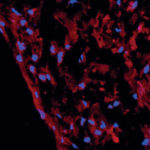

Cellule staminali della polpa dentale

di Barbara Zavan

Laureata in scienze biologiche con 110/110 e lode, dottorato in «Ingegneria dei tessuti e dei trapianti» presso l’Università degli Studi di Padova.

Professoressa...